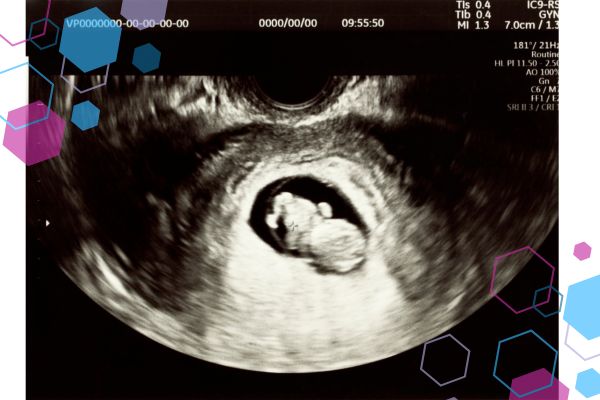

If you’re in the first trimester, it can feel too early to think about birth — and at the same time, impossible not to.

The first trimester is usually framed around nausea, fatigue, scans, and “getting to 12 weeks”. What gets far less attention is what’s happening cognitively and emotionally.